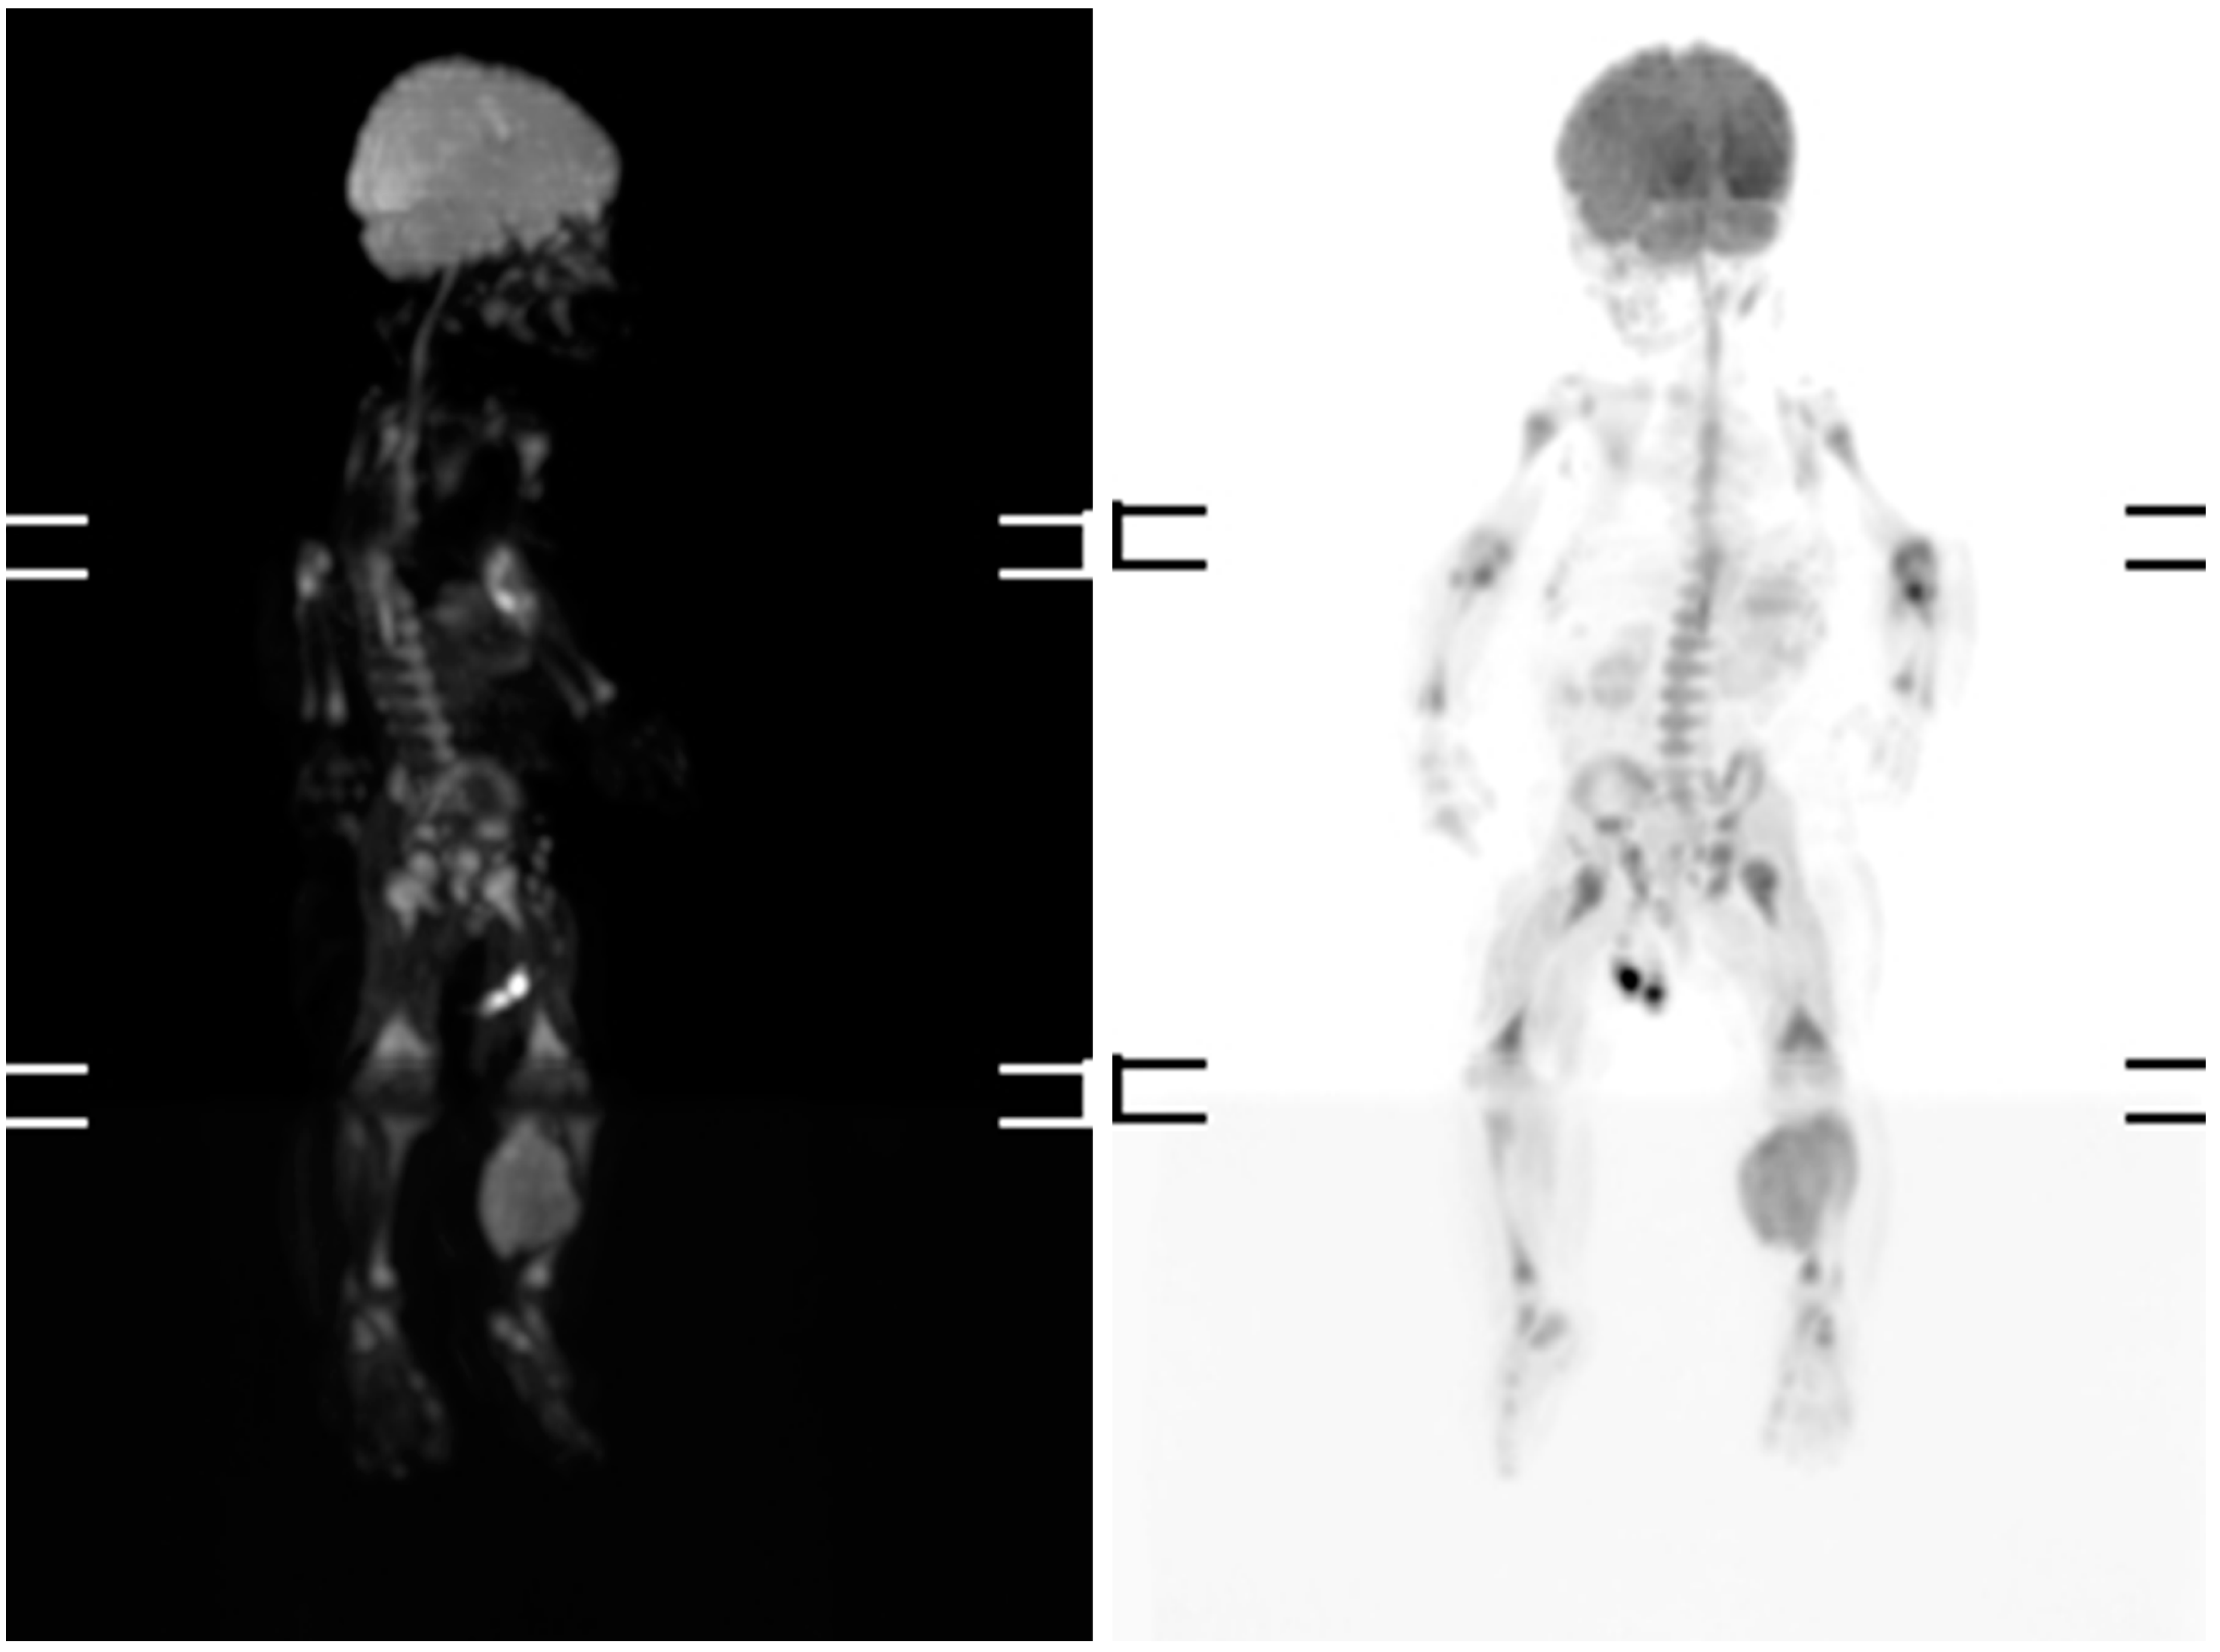

Magnetic resonance imaging (MRI) and scintigraphy determined a soft tissue tumor in the soleus muscle, while biopsy confirmed embryonal rhabdomyosarcoma with high mitotic activity (Ki67 (monoclonal antibodies) ~80%) (Figure 1 and Figure 2).

Figure 1. Scintigraphy at three months old, revealing a soft tissue mass in the left calf.